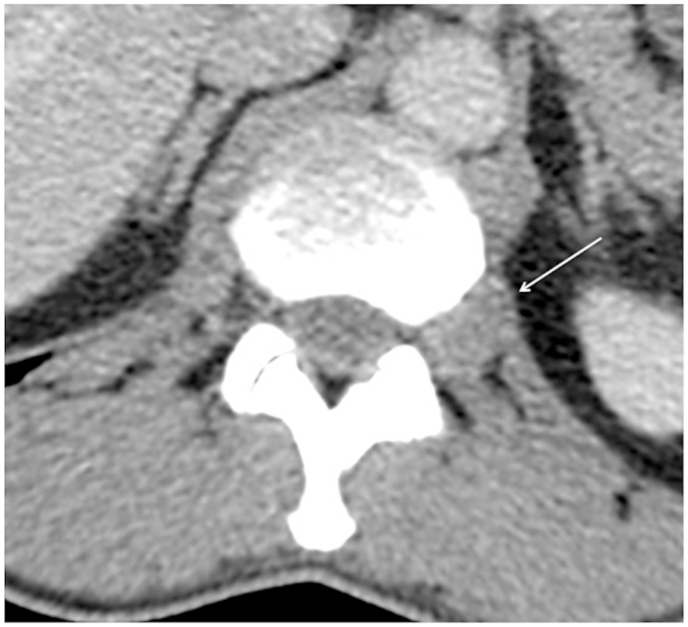

Fig. 2.

Axial CT with soft tissue window settings at the T12/L1 level. A soft tissue density eccentric bulge of the intervertebral disc contour displaces the left extraforaminal fat. It contacts and posteriorly displaces the left extraforaminal T12 nerve root.